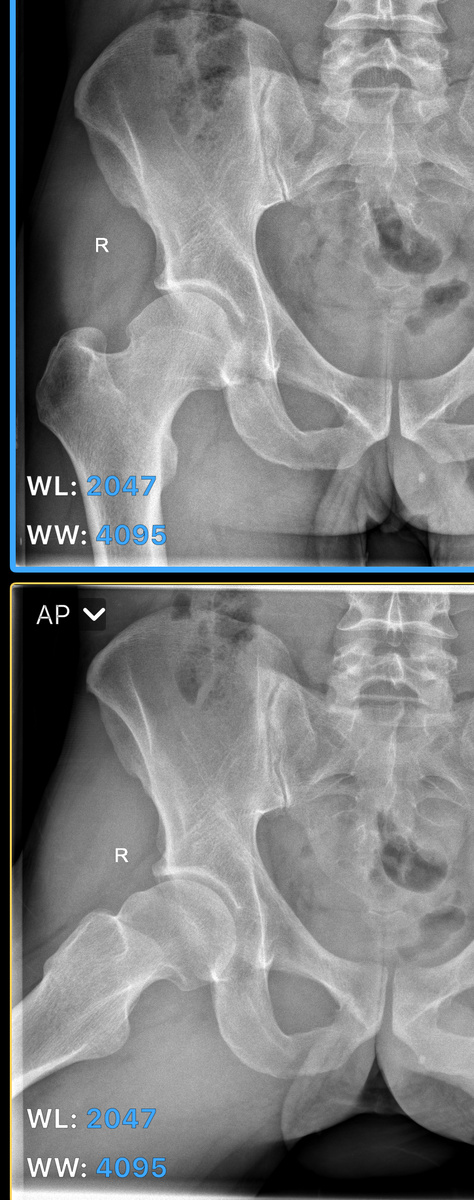

Фемороацетабулярный импиджмент или ФАИ.

Беспокоит боль в паховой области? Бывает чувство «замыкания» сустава? Возможно, это ФАИ (FAI)- по сути своей конфликт между бедренной костью и вертлужной впадиной. А в чем же причина конфликта? ФАИ ассоциирован с изменением морфологии тазобедренного сустава, который напомню представлен головкой бедренной кости покрытой гиалиновый хрящом и вогнутой частью вертлужной впадины, так же покрытой гиалиновым хрящем, а по периферии имеющей фиброзную структуру- суставную губу. Выделяют 2 варианта ФАИ, зависящих от места измененной структуры: САМ/кулачок- когда идет утолщение в области шейки бедренной кости и PINCER/клещи-  избыток покрытия головки вертлужной впадиной сустава.  Что же провоцирует ФАИ или факторы риска? Например: у хоккеистов, спринтеров, футболистов. Стресс (нагрузка )—-> травма—>воспаление—> перестройка (утолщение) участка шейки бедра или вертлужной впадины. 2.Дисплазия тазобедренного сустава. Как заподозрить? Боль в бедре или паху, возникающая при определенном движении; с

Выделяют 2 варианта ФАИ, зависящих от места измененной структуры: САМ/кулачок- когда идет утолщение в области шейки бедренной кости и PINCER/клещи-  избыток покрытия головки вертлужной впадиной сустава.

Рентген костей таза с захватом верхней трети бедренных костей в прямой и боковой проекциях.